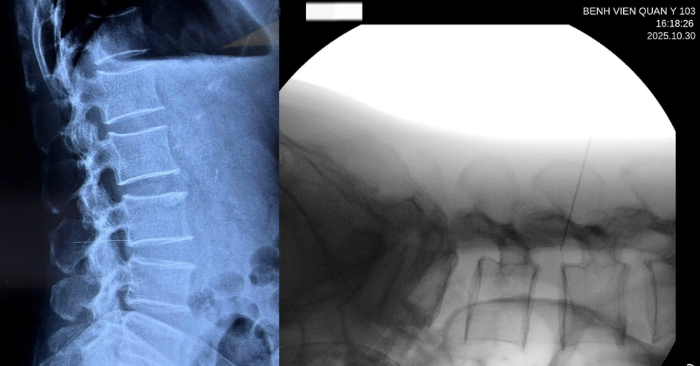

Dị vật kim gãy đâm vào đốt sống

Ngày 30/10, Bệnh viện Quân y 103 tiếp nhận bệnh nhân H.T.G. (52 tuổi, trú tại Hà Nội) trong tình trạng đau lưng cấp, đi lại khó khăn. Qua thăm khám, các bác sĩ phát hiện nhiều nốt kim châm quanh vùng thắt lưng. Kết quả chụp X-quang cho thấy có dị vật kim loại dài khoảng 6cm cắm sâu dọc theo thân đốt sống.

Bệnh nhân cho biết trước đó tự châm cứu để giảm đau, tuy nhiên một đoạn kim đã gãy, xuyên sâu vào cột sống. “Một phần kim cắm hướng vào ổ bụng, rất may chưa gây tổn thương các tạng lân cận”, TS.BS Hoàng Thanh Tùng – Chủ nhiệm Khoa Chấn thương Chỉnh hình cột sống, Bệnh viện Quân y 103 cho biết. Sau khi chụp chiếu và đánh giá đủ điều kiện phẫu thuật, ê-kíp bác sĩ đã tiến hành mổ lấy dị vật ra.